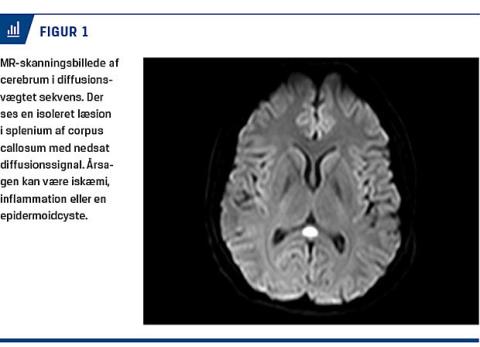

På en MR-skanning blev der fundet en læsion i splenium af corpus callosum, som var hyperintens på fluid attenuated inversion recovery (FLAIR)-sekvensen og viste diffusionsindskrænkning på den diffusionsvægtede sekvens (Figur 1). Patienten blev behandlet empirisk i fem dage med peroralt givet prednisolon 1 mg/kg på mistanke om varicella zoster-associeret vaskulitis og derudover med 75 mg acetylsalicylsyre. Denne behandling var planlagt til at vare tre måneder.

Isolerede spleniuminfarkter er sjældne, men der er set reversible centrale læsioner i splenium ved bl.a. virusencefalopatier, og det er da tolket som ødem eller inflammation snarere end som værende på baggrund

af iskæmi. Disse læsioner har givet milde symptomer med en god prognose [5].